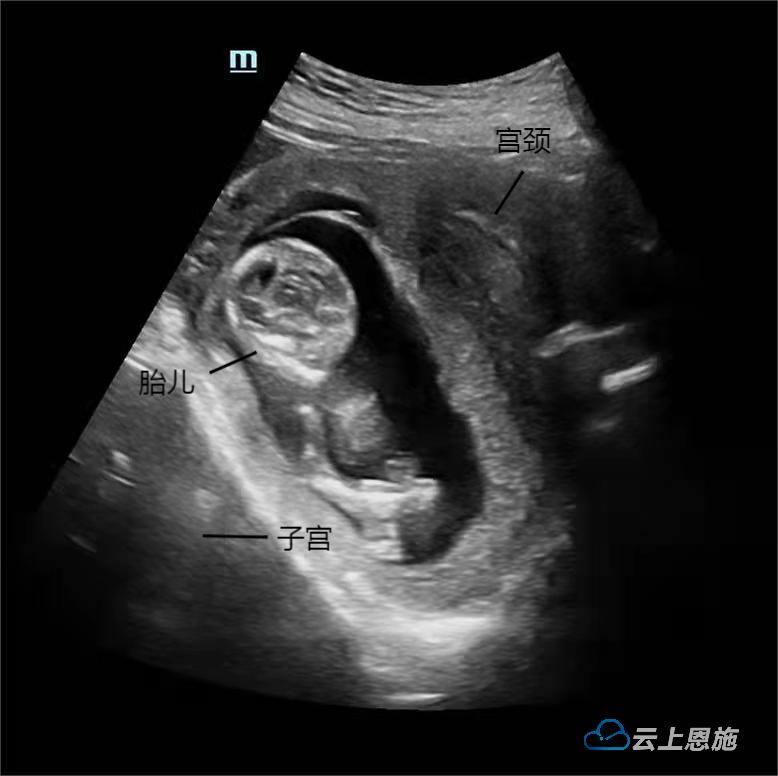

云上恩施报道(融媒体记者 袁润 通讯员 刘铁强 侯丹丹 杨名)近日,怀孕13周+1天的游女士因“反复排尿困难8天”来到恩施州中心医院妇儿医院就诊。游女士告诉值班医生,之前已在其他医院接受过住院治疗,但效果不理想。鉴于患者的情况,值班医生当即为游女士办理住院。经该院产科详细检查后,确认游女士的情况为妊娠合并子宫箝闭(图1、图2)。

图1 妊娠子宫后位嵌顿示意图

医生介绍,妊娠子宫箝闭是一种罕见的产科并发症。正常子宫孕14-16周时会自盆腔延伸到腹腔,罕见的情况下,子宫呈持续后位状态,未能上升进入腹腔,而是固定在骶窝处。随着时间推移,宫颈将被上提,导致膀胱和尿道受压变形,造成膀胱出口梗阻,导致尿液排出不畅,即子宫箝闭症。这是产科急诊中罕见但又非常严重的并发症,发病率为 1/3000~1/10000,若未能识别或及时处理子宫循环障碍,可导致自然流产、早产、胎儿生长受限,甚至膀胱破裂、子宫破裂,胎儿损失率约 33%。所以,妊娠期及时诊断和治疗尤为重要。